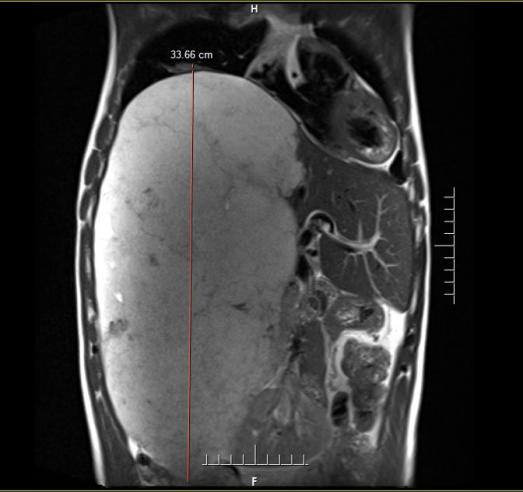

術(shù)前MRI提示肝臟巨大占位,縱向直徑約34cm,直抵盆腔

近段時(shí)間,李先生因上腹持續不適前往中國科大附一院就診。全面的影像學(xué)檢查結果讓他和家人震驚不已——腹腔里竟然長(cháng)了一個(gè)巨大的占位性病灶,縱向直徑約34厘米,從上腹一直延伸至盆腔,如同懷胎十月的胎兒般占據了腹腔大量空間,最終確診為“肝臟巨大占位(肝血管瘤可能)”。